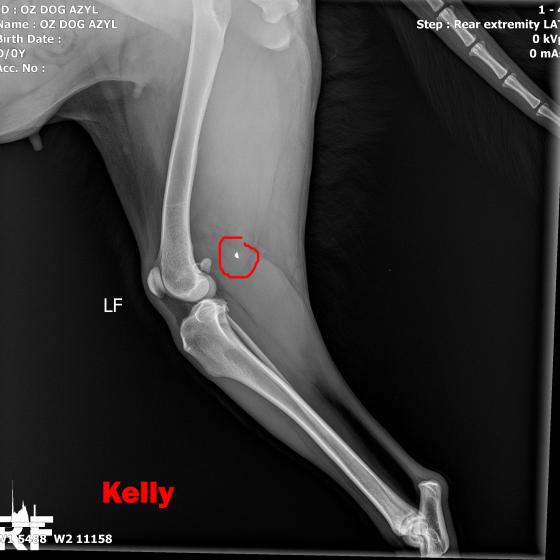

Image removed.KELLY - Vzali sme ju v rámci záchrannej akcie ČSKP z ranča, kde boli zvieratá v hororových podmienkach. Jedli, čo si našli, nekontrolovane sa medzi sebou množili a vôbec nie je vylúčené, že aj na ostatných si nejaký zlomyslený človek skúšal streľbu do diaľky. Kelly je úžasná, pokorná, mierumilovná, oddaná fenka, ktorá sa tak strašne zmierila s utrpením a svojim životom, že celé dni len tíško preleží v peliešku a občas si poplačká. Užíva si každé pohladenie, ale nechce byť nenásytná lebo nevie, či sa jej aj zajtra ujde. Ťažko je ju pohladiť bez toho aby Vám pri nej slza nevytiekla. Nevieme a nechceme si ani len predstaviť akým peklom si musela už prejsť. Kelly má diagnóz hneď niekoľko. Jej primárnym problémom je hrozné krívanie, doslova hopká ako zajko. Neudrží sa na zadných nohách. Môže to spôsobovať hneď niekoľko faktov.

V ľavej packe, medzi druhým a tretím prstom mala brok (treba si to predstaviť, ako keď máte kamienok v topánke a nech stúpate akokoľvek, vždy Vás tlačí. Lenže to je len kamienok a nie cudzí predmet v živom tkanive. Tú bolesť si radšej ani nepredstavujte.) V tej istej nožičke, v oblasti zadnej strany kolena bol ďalší brok, ktorý jej tiež prekážal pri narovnaní nohy. Prvým krokom bolo odstránenie týchto dvoch brokov, ktoré pravdepodobne spôsobovali najväčšie ťažkosti. Operácia sa konala 10.5.2020, dopadla výborne, Kelly sa zotavuje.

Píšeme ale "pravdepodobne" preto, lebo Kelly má tiež problém s krížovým väzom v kolene, ktorý má známky deformácie a má tiež hypointenzitu disku (to znamená, že má na platničke medzi stavcami pruh, ktorý vyčnieva a tlačí na miechu). Veríme, že vsetci strážni anjeli pri nej budú stáť a zvládne sa zotaviť, aby si mohla užívať taký život, aký mala žiť od narodenia. My sme pri nej, zabezpečíme jej všetko potrebné! Za diagnostiku, MRI a chirurgiu máme dve faktúrky, v celkovej výške 762,05€.